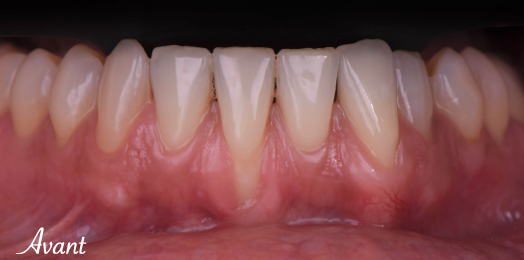

Traitement des récessions gingivales des incisives mandibulaires

Description détaillée du lambeau déplacé coronairement associé à un greff on de tissu conjonctif Le traitement des récessions gingivales dans le secteur antérieur mandibulaire s’avère

Si vous présentez un de ces signes, c’est peut-être parce que vous avez une récession gingivale, une rétraction et perte progressive de la gencive qui entraîne l’exposition de la racine de la dent.

Le recouvrement de la racine a été obtenu par une technique de lambeau déplacé coronairement, qui consiste à déplacer la gencive du bas vers le haut.

Un greffon prélevé au palais a également été ajouté en dessous pour épaissir la gencive et la rendre plus résistante dans le temps.